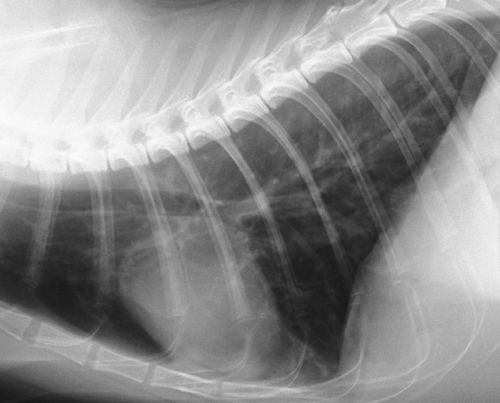

次にイメージングプレートのCRレントゲンとFPDによるDRレントゲンの画像比較をしてみたいと思います。下の写真はそれぞれ同じ猫の正常な胸部レントゲン写真です。違いがお分かりになるでしょうか?

上がCRで下写真が次世代のDRによるものです。

DRレントゲンの画像の方がくっきり明瞭に見える一方、CRではやや曖昧な印象を受けると思います。